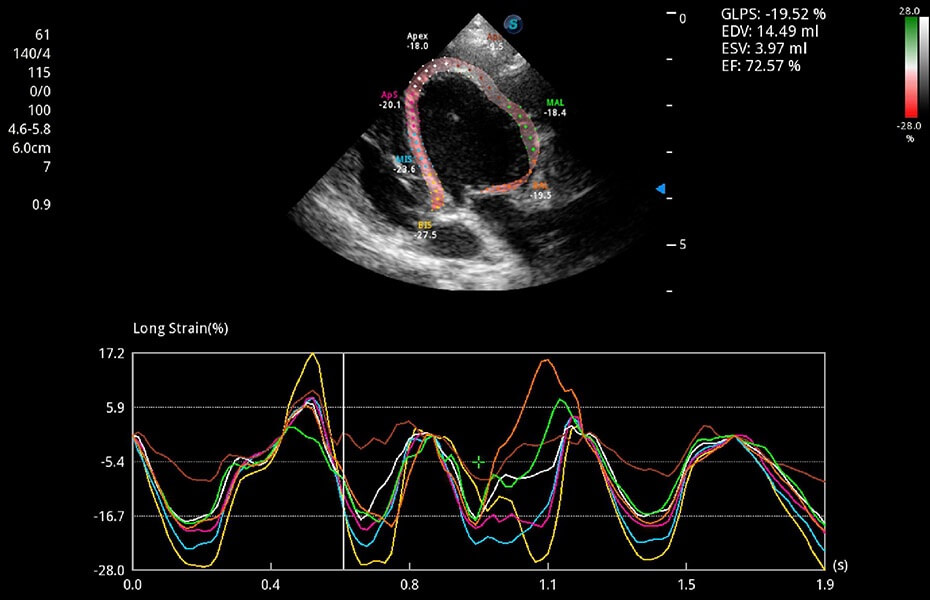

ProPet 60 作為一款高端臺式動物超聲設(shè)備,為動物醫(yī)生的日常診斷提供了一系列貼合動物臨床需求、解決臨床實際問題的高級成像功能。憑借全系列高清探頭,滿足醫(yī)生對腹部、心臟、生殖、淺表、肌骨等成像的所有需求,切實幫助您提升檢查效率,提高診斷信心。